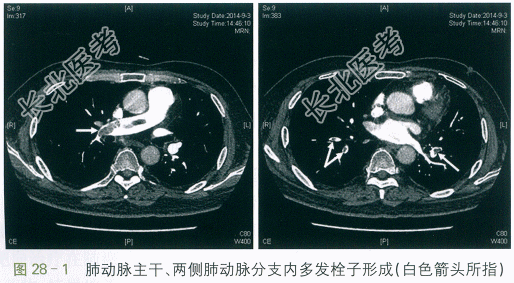

/L。X线胸片示:两肺未见活动性病变。D-二聚体:15.78mg/L。进一步行CT肺动脉造影示:肺动脉主干、两侧肺动脉分支内多发栓子形成。遂予以收治入院。2.既往史

CT肺动脉造影示:肺动脉主干、两侧肺动脉分支内多发栓子形成(见图28-1)。